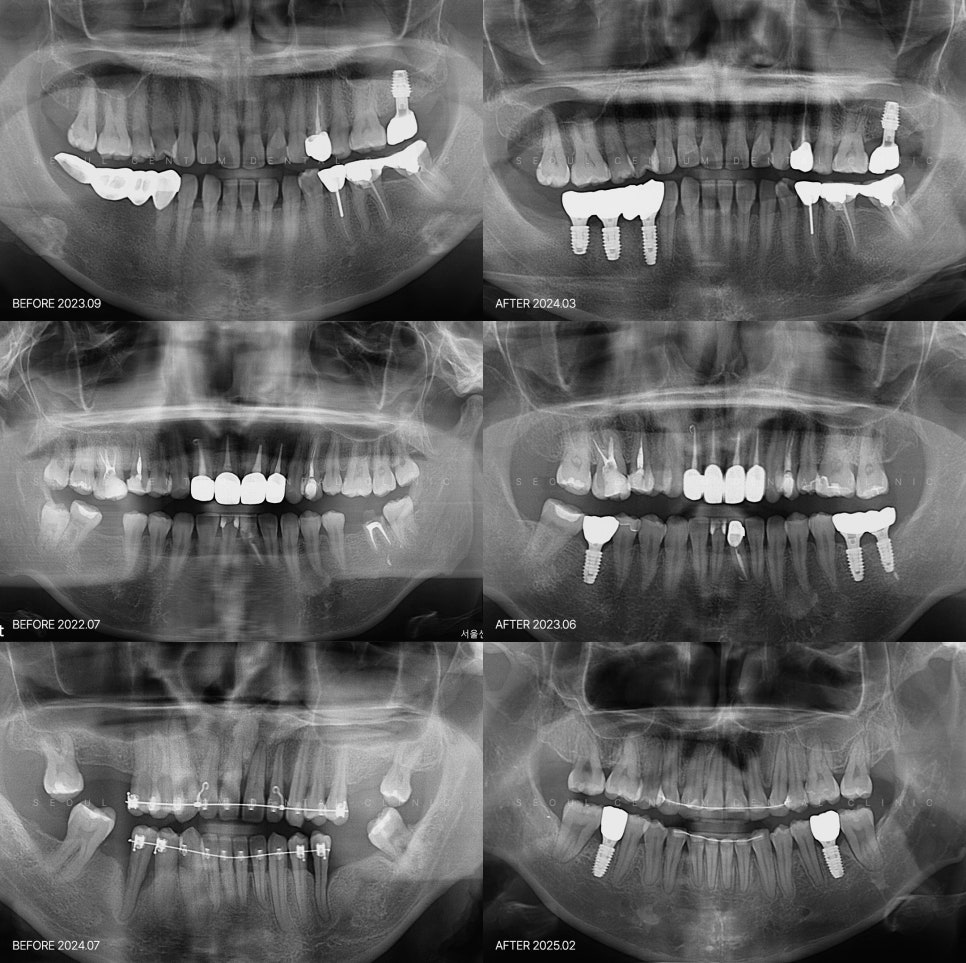

서울센텀치과에서는 필수로 3가지를

확인하고 있습니다.

미세균열이 있는지 없는지 확인합니다.

깨진 조각 옆으로 금이 이어져 있는지

꼭 확인을 하고요.

두 번째로 어금니에서 많이 힘을 받는

봉우리 부분이 깨진 것이라면

나중에 더 크게 깨지는 것을 꼭 방지합니다.

세 번째로 왜 이 치아가

깨졌는지를 체크하는데요.

만약 치아가 깨질만한 이갈이, 이악물기

등의 습관이 있는 경우라면

또 깨질 확률이 있기 때문입니다.